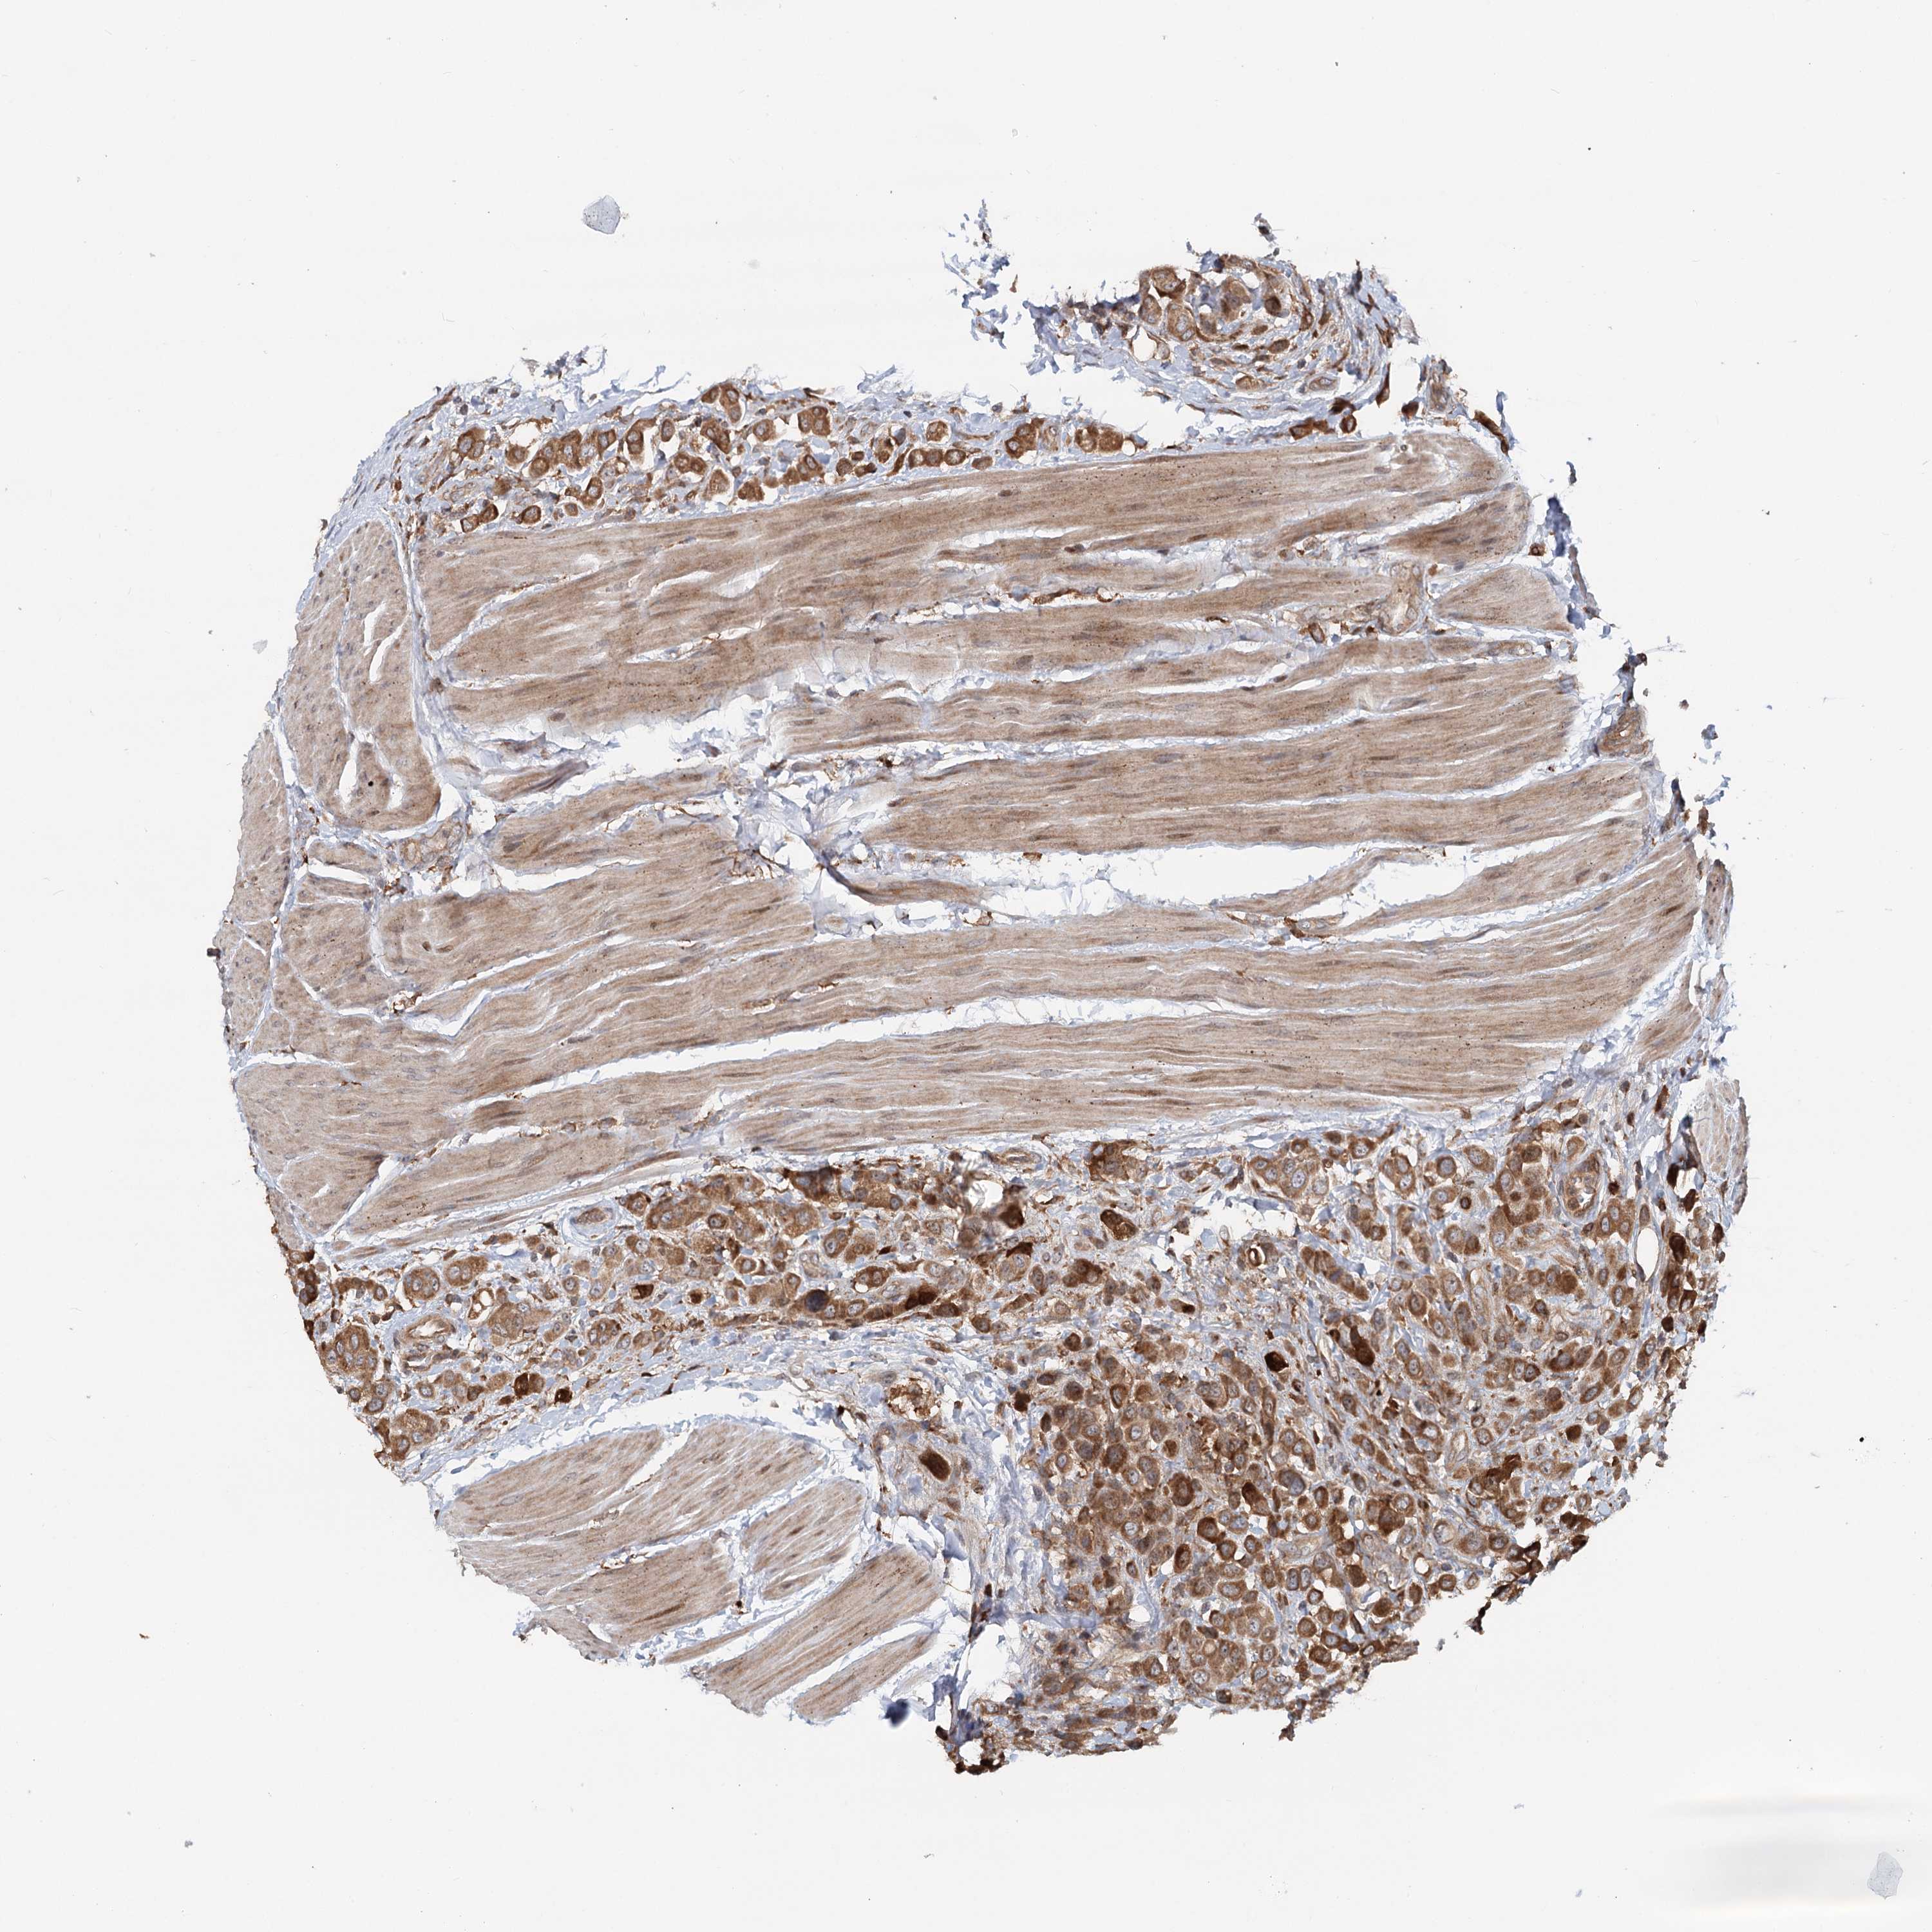

UROTHELIAL CANCER - Protein expressioni

A mouse-over function shows sample information and annotation data. Click on an image to view it in a full screen mode. Samples can be filtered based on level of antibody staining by selecting one or several of the following categories: high, medium, low and not detected. The assay and annotation is described here.

Note that samples used for immunohistochemistry by the Human Protein Atlas do not correspond to samples in the TCGA dataset.

Antibody stainingi

Antibody staining in the annotated cell types in the current human tissue is reported as not detected, low, medium, or high, based on conventional immunohistochemistry profiling in selected tissues. This score is based on the combination of the staining intensity and fraction of stained cells.

Each image is clickable and will lead to virtual microscopy that enables deeper exploration of all samples and also displays staining intensity scores, fraction scores and subcellular localization as well as patient and tissue information for each sample.

Antibody HPA038576

Antibody HPA038577

Staining

High

Medium

Low

Not detected

Intensity

Strong

Moderate

Weak

Negative

Quantity

>75%

75%-25%

<25%

None

Location

Nuclear

Cytoplasmic/membranous

Cytoplasmic/membranous,nuclear

Urothelial carcinoma, High grade

Urothelial carcinoma, Low grade

Urothelial carcinoma, NOS